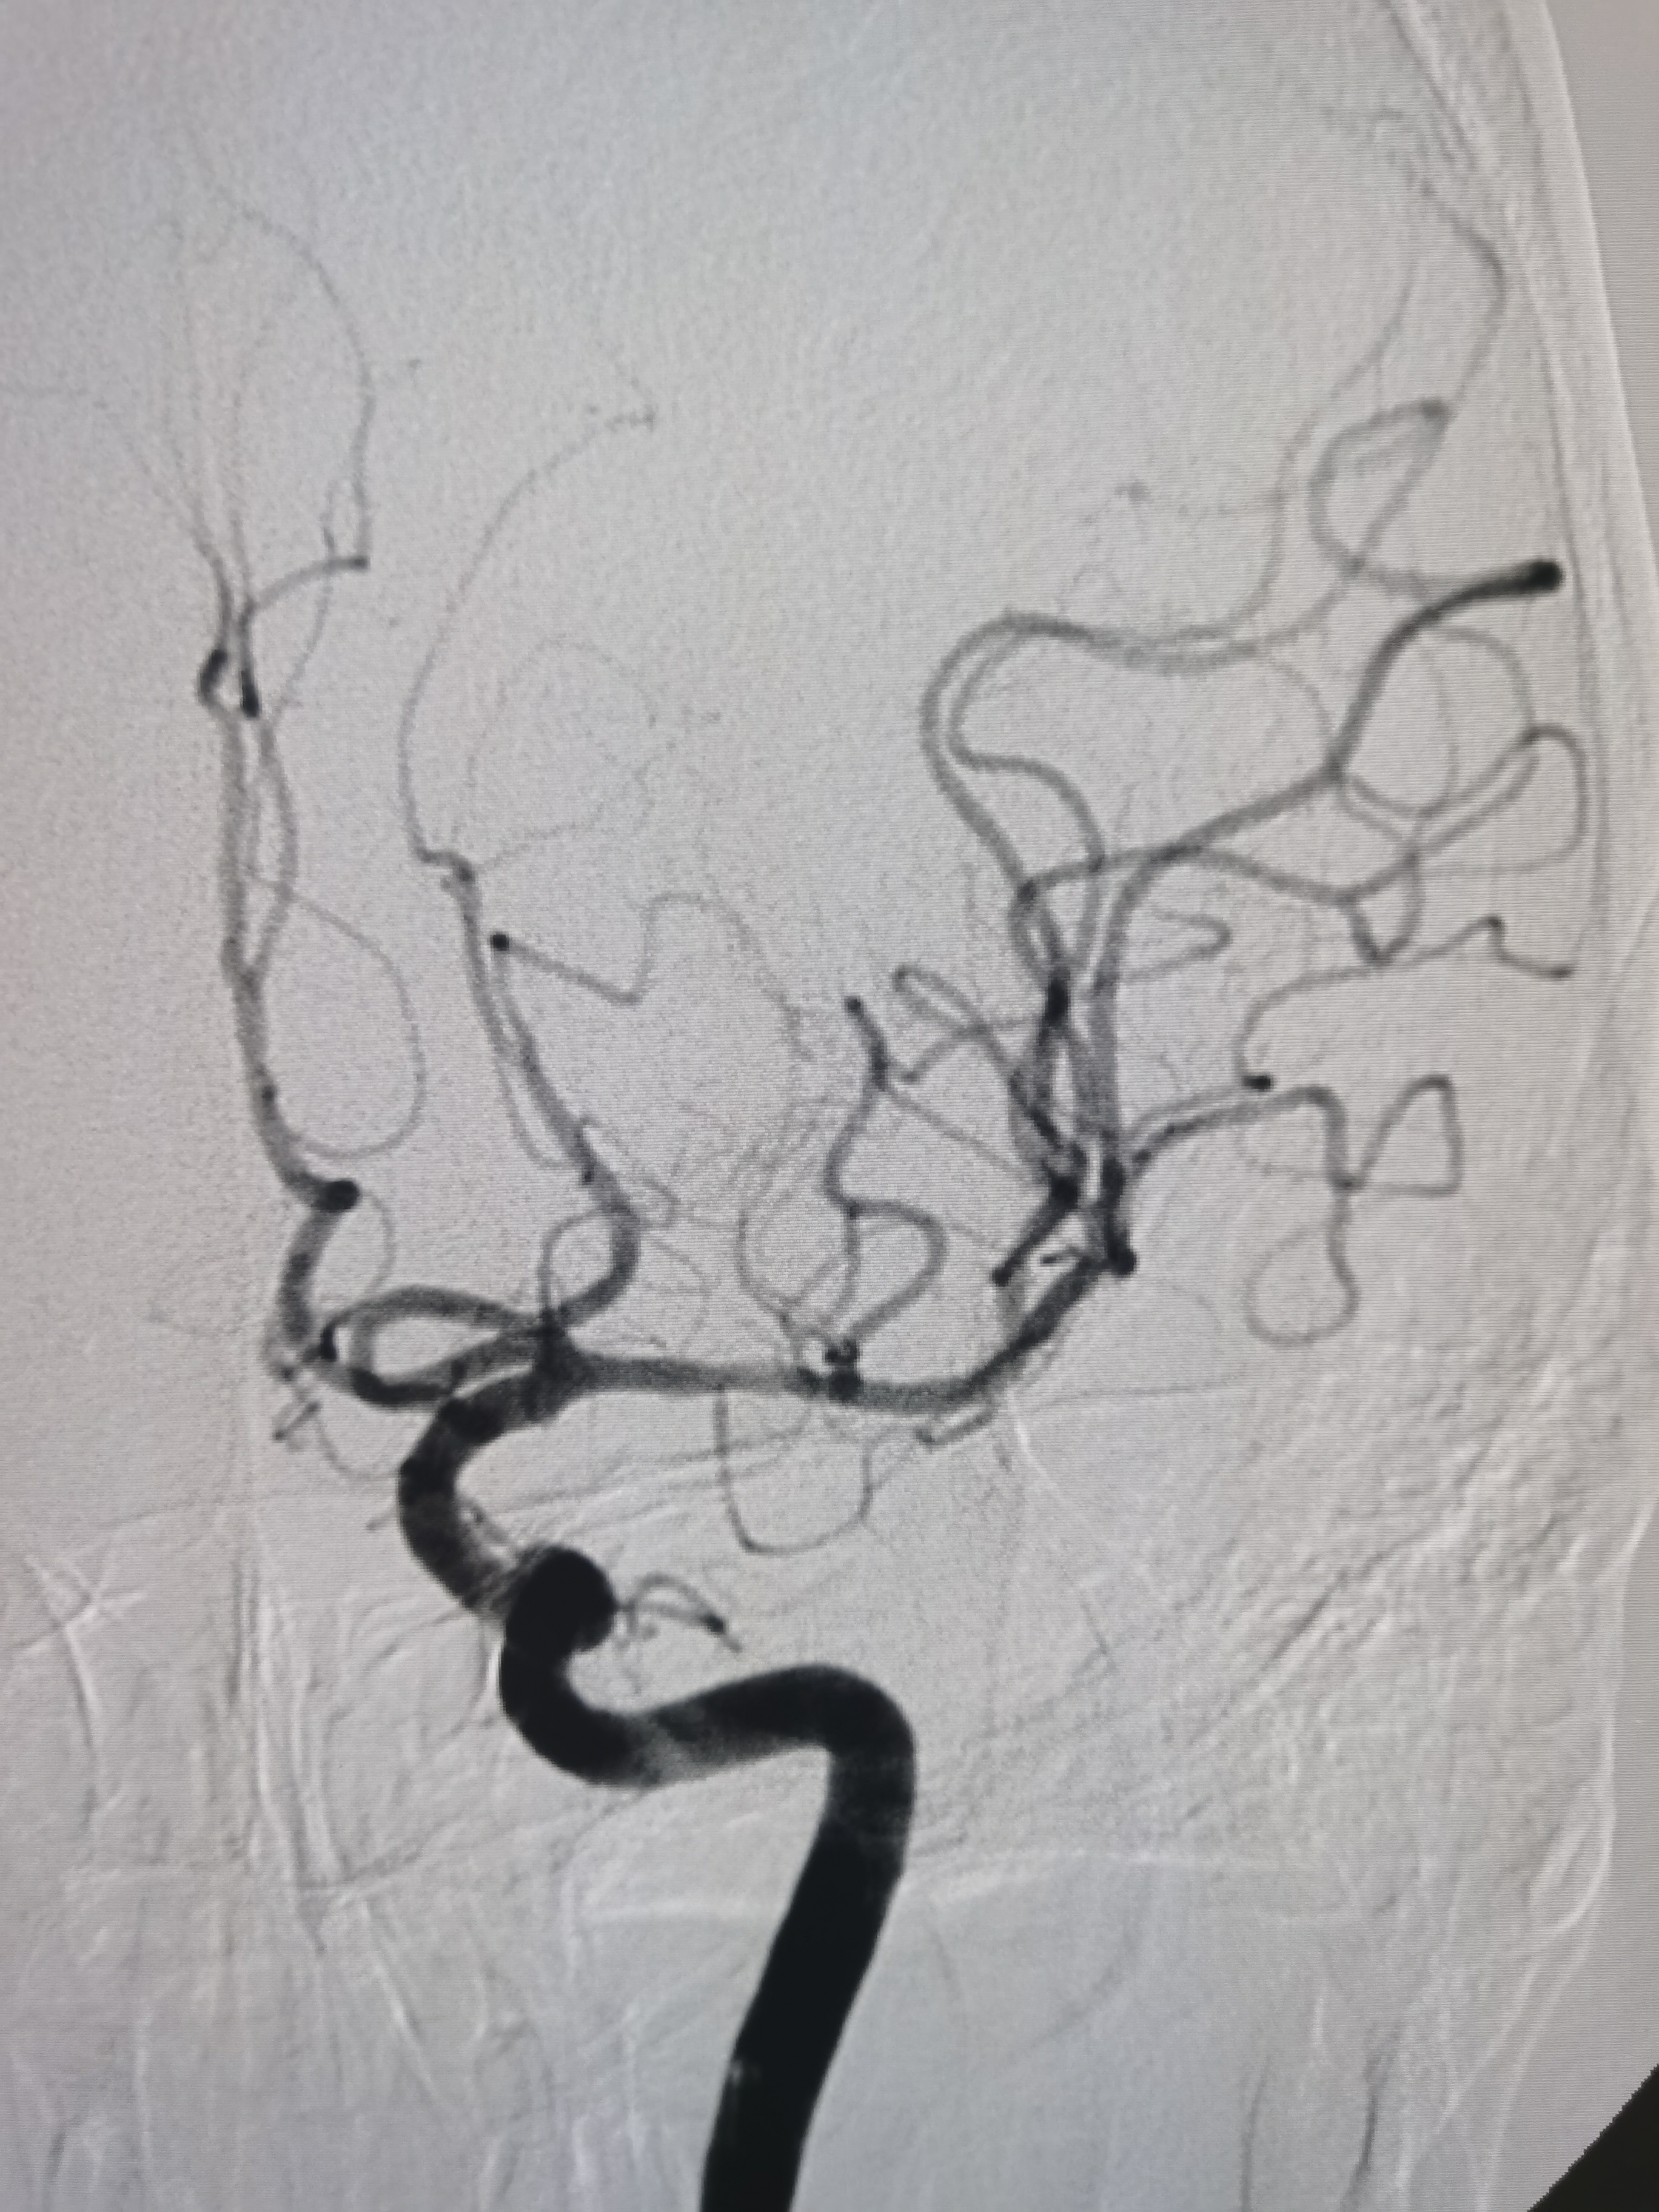

4/20取栓支架释放后血管再通。

SWIM技术取栓一次,取出的血栓。

取栓后颅内血管再通,血流通畅。

患者穿刺到再通15分钟,术后颅内血流通畅,TICI3级,撤出各级导管结束手术。继续内科药物治疗,观察病情。